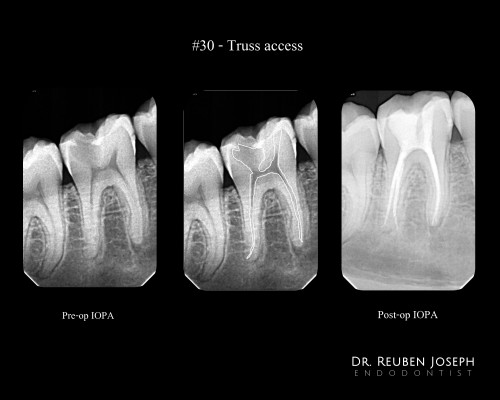

Desi- Image guided endodontics

By Reuben Joseph / June 27, 2018

#30 – Truss Access Pre-op IOPA reveals a #30 with irreversible pulpitis involving the distal pulp […]